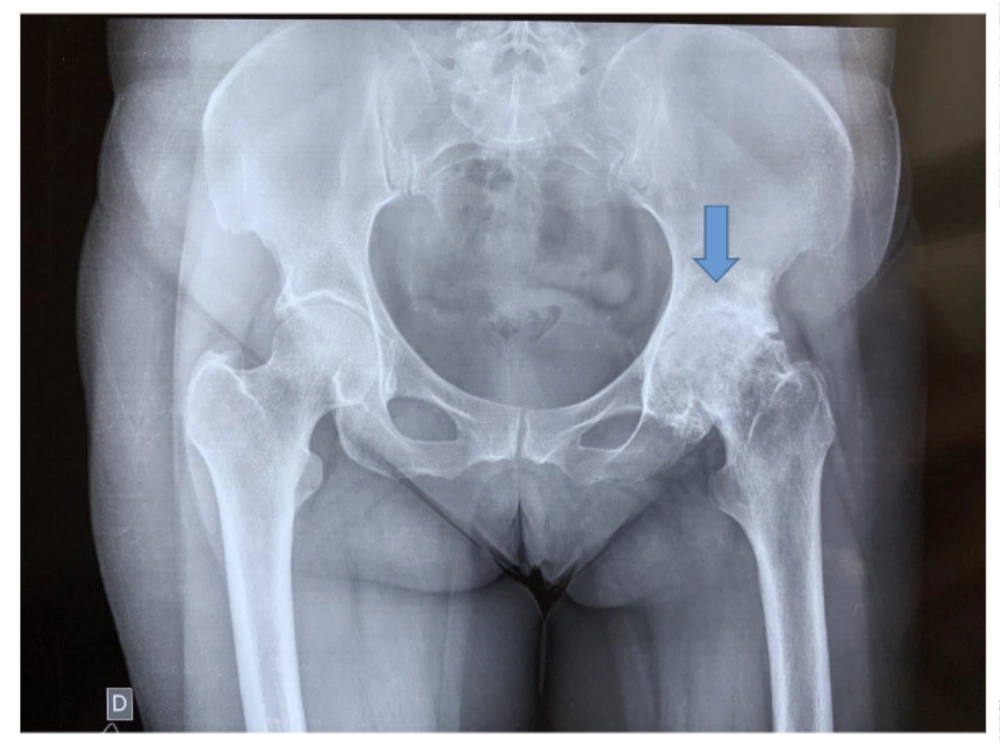

Rx demonstrando uma artrose grave de quadril esquerdo, paciente já com limitação e dor importante para caminhar e com dificuldade para atividades básicas do dia a dia.

Artrose severa do quadril esquerdo – seta.